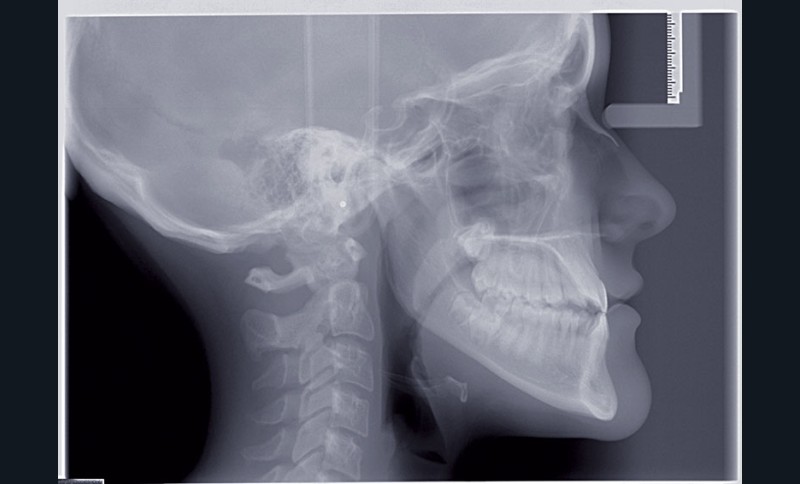

Nous sommes en présence d’une patiente en fin de croissance faciale, âgée de 16 ans. Elle présente une classe III dentaire et squelettique associée à une asymétrie faciale de type latérognathie mandibulaire avec déviation des points interincisifs et déviation du menton vers la gauche.

Pour des raisons personnelles, la patiente refuse un protocole orthodontico-chirurgical. Nous optons pour une réduction de la classe III par compensations dento-alvéolaires car la progénie n’est pas très importante et nous estimons que le résultat dentaire, squelettique et facial peut être cohérent. Un système « Motion Classe III Carriere » va être utilisé suivi d’un appareillage multibague « Carriere SLX ».